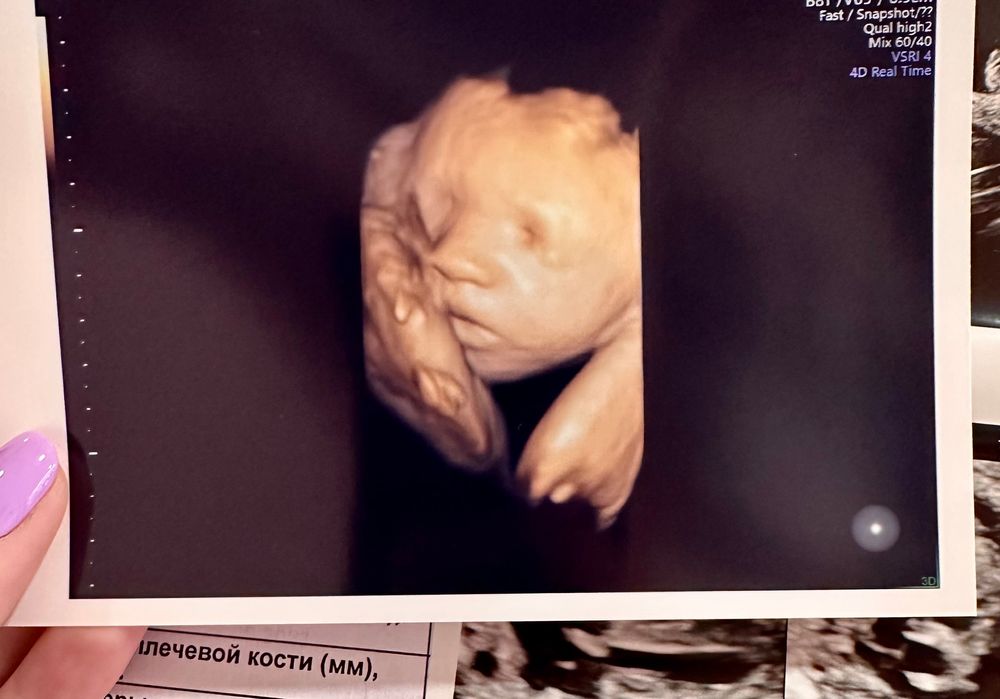

4D узи в 26 недель и 6 дней 🫶🏼💓

Урааа, в эту беременность малышка повернулась личиком и полностью дала себя обсмотреть ☺️

Очень хотела посмотреть на носик, т.к гипоплазия и размер косточек очень маленький.

Весит малышка примерно 913 грамм 💟

Сидит на попе, но и времени перевернуться в головное предлежание еще с запасом 🙏🏻